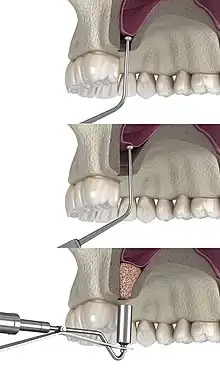

Traditional sinus augmentation or lateral window technique

The procedure is performed from inside the patient's mouth where the surgeon makes an incision into the gum, or gingiva. Once the incision is made, the surgeon then pulls back the gum tissue, exposing the lateral bony wall of the sinus. The surgeon then cuts a "window" to the sinus, exposing the Schneiderian membrane. The membrane is separated from the bone and bone graft material is placed into the newly created space. The gums are then sutured closed and the graft is left to heal for 4–12 months.[6]

The graft material used can be either an autograft, an allograft, a xenograft, an alloplast, synthetic variants, or combinations thereof.[7] Studies indicate that the mere lifting of the sinus membrane, creation of void space, and blood clot formation might result in new bone due to the principles of guided bone regeneration.[8] The long-term prognosis for the technique is estimated to 94%.[9]